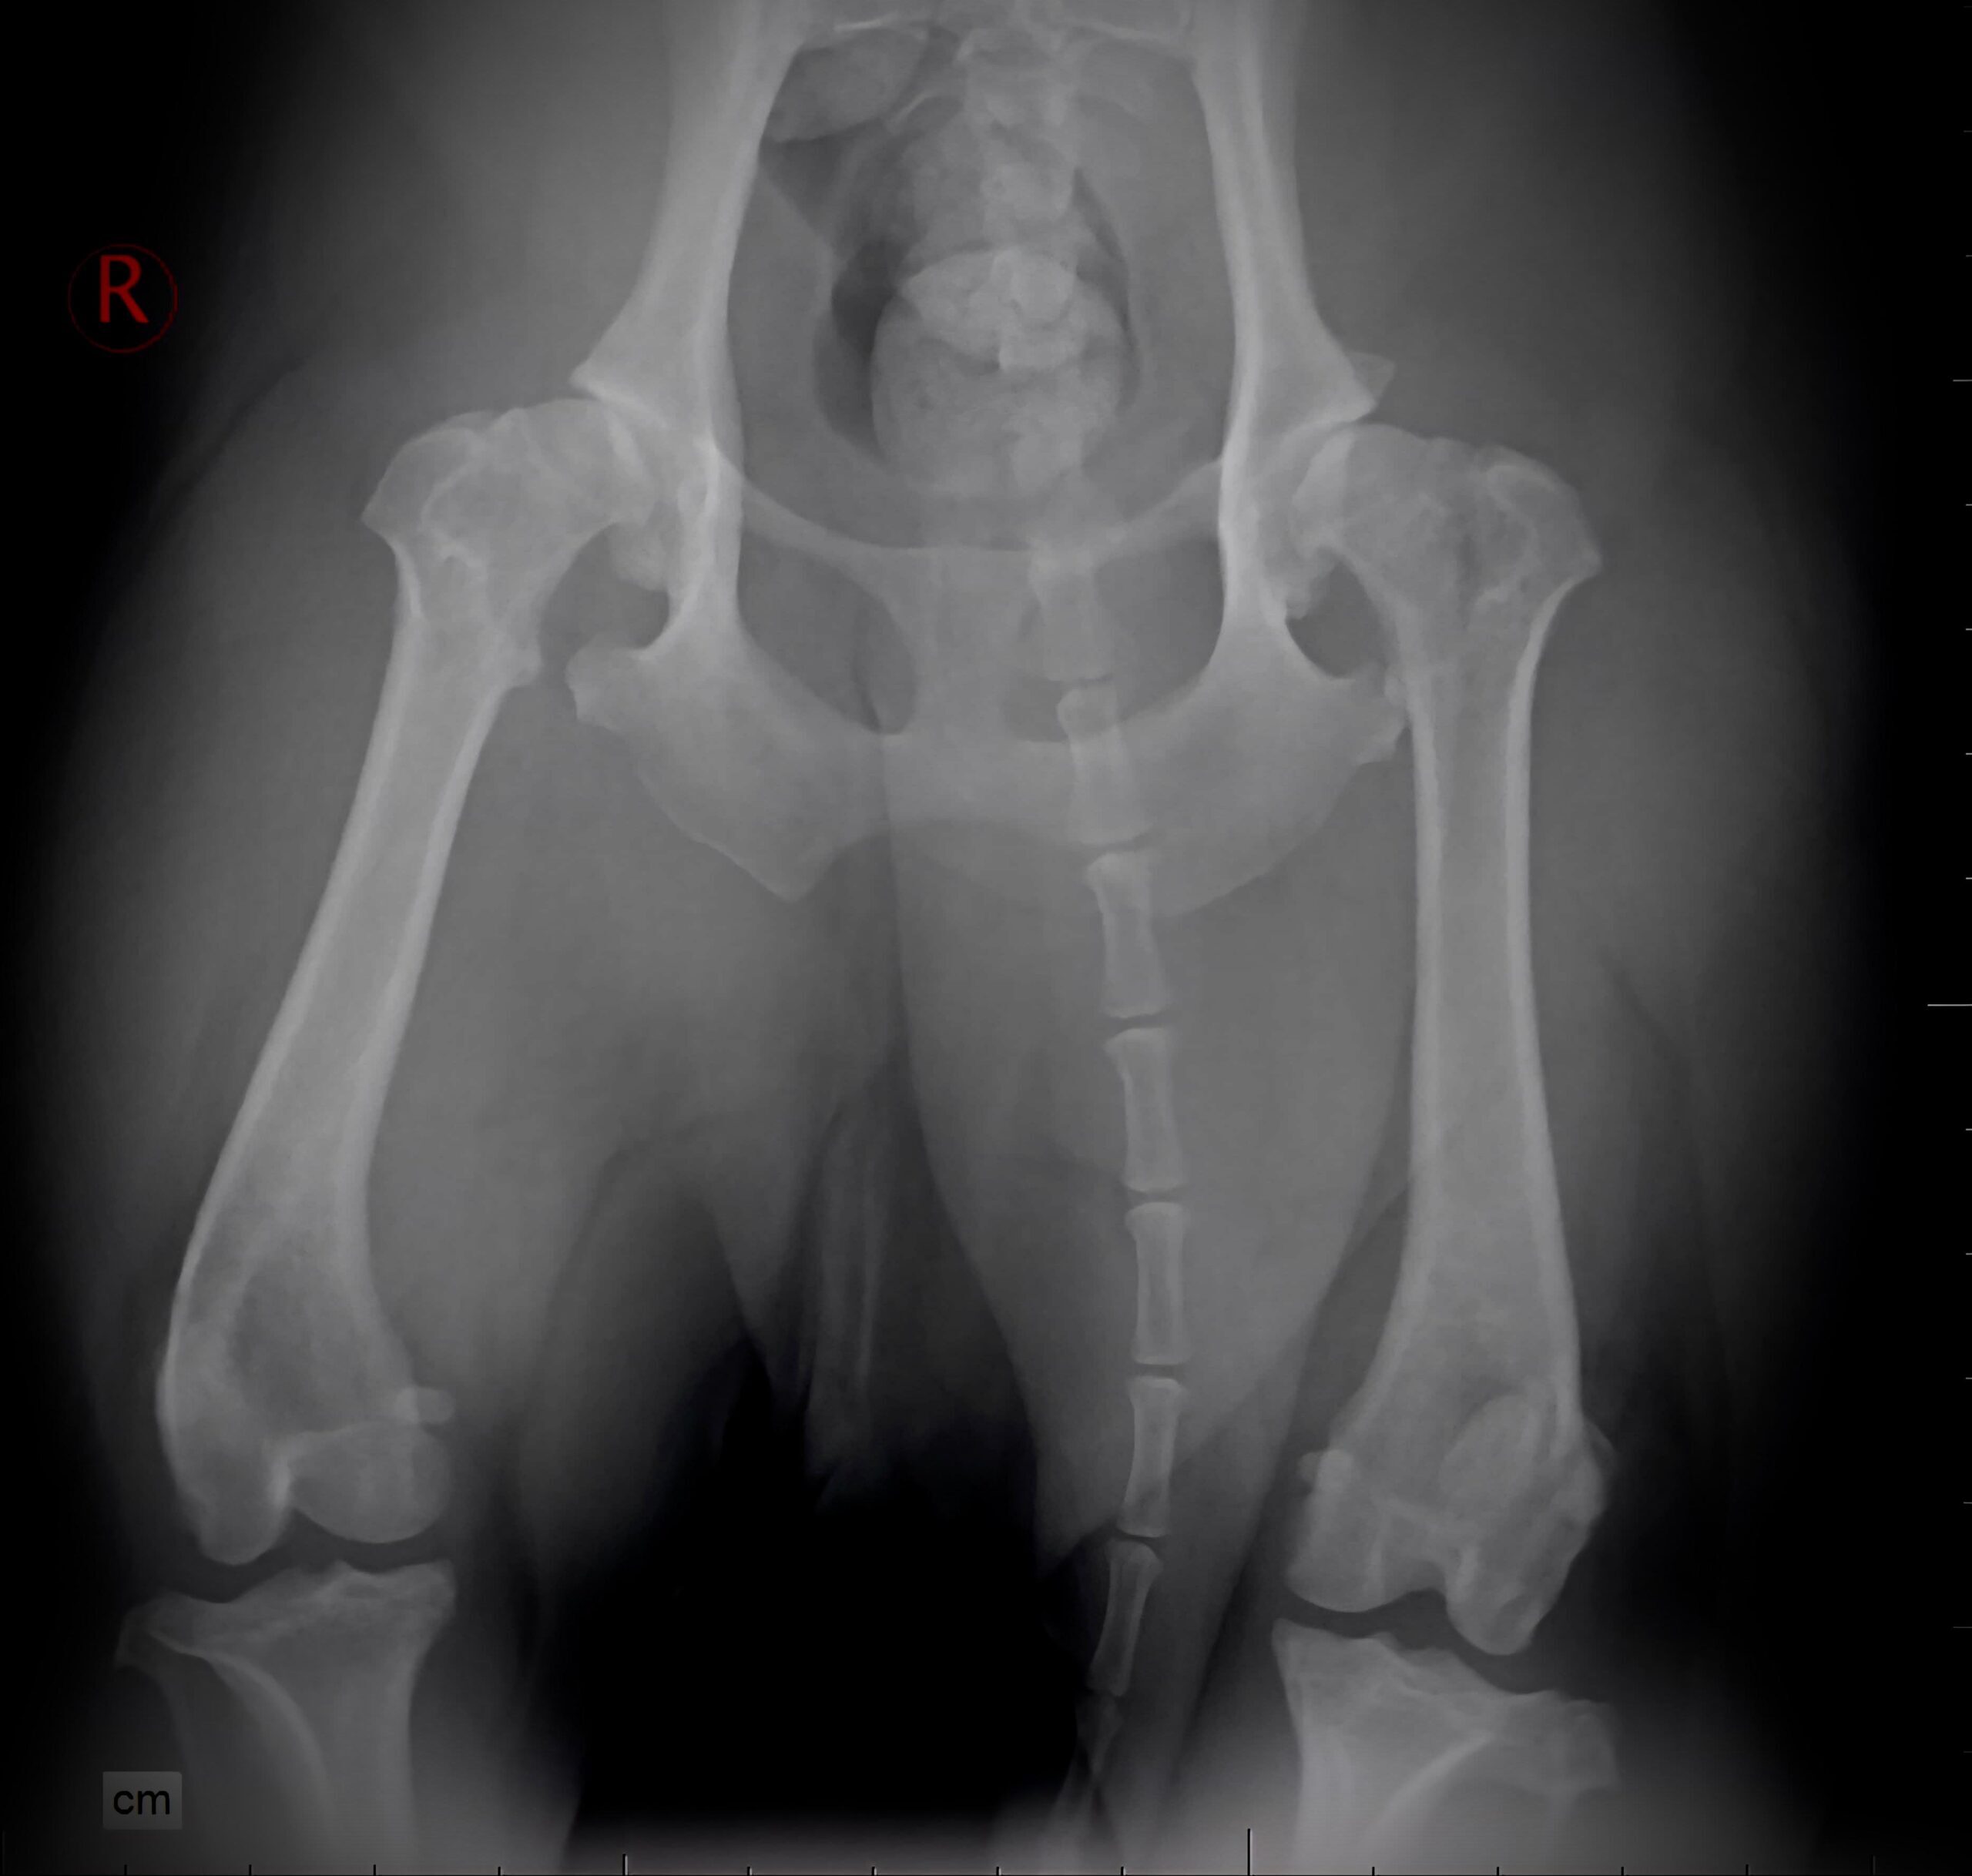

Pe toate acestea le găsiți în prima rețea de medicină veterinară, The Vets. Vă așteptăm în spital și în oricare dintre clinicile noastre, cu prietenul vostru necuvântător. Aici, el va primi toată îngrijirea și atenția, fie că are nevoie de o intervenție chirurgicală, de analize, imagistică medicală, tratament sau doar de un consult medical veterinar. Aici vă așteaptă medici cu mii de cazuri rezolvate cu succes, laboratoare digitale de analize și facilități moderne de internare.